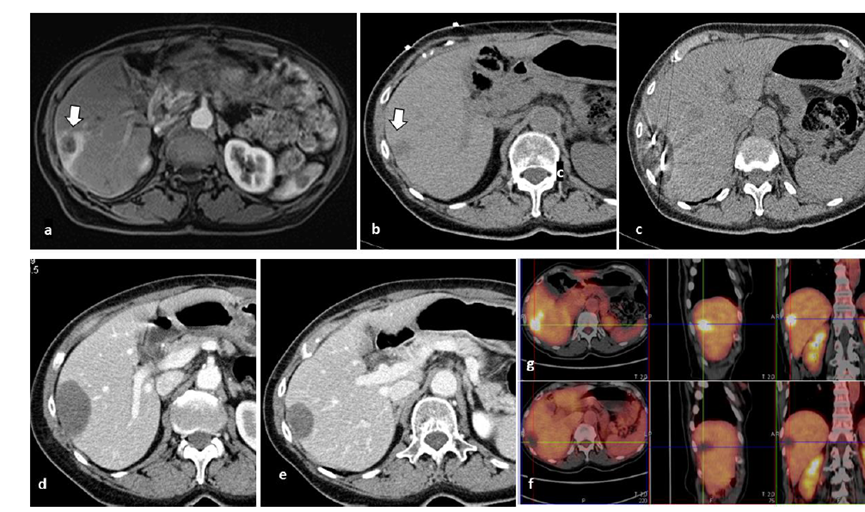

79 歲男性,肝轉(zhuǎn)移(結(jié)直腸癌)腫瘤的完全消融病例

( a ) 軸向 MRI 和 ( b ) 軸向 CT 顯示肝S8段有一個(gè)16mm的病灶,鄰近肝緣。( c )冷凍消融期間CT顯示放置了2個(gè)冷凍探針,低密度冰球包圍病灶。(d)術(shù)后1個(gè)月隨訪 CT顯示冰球?qū)?yīng)的壞死區(qū)域,未見復(fù)發(fā)。(e)術(shù)后6個(gè)月的CT,壞死區(qū)域縮小,未見復(fù)發(fā)。(f)與基線影像(g)相比,12個(gè)月后的FDG-PET/CT顯示未見FDG攝取。

62歲女性,肝轉(zhuǎn)移(卵巢癌)腫瘤的完全消融病例(a)軸向CT顯示病變位置毗鄰心臟和上腔靜脈(黑色箭頭)。(b)術(shù)中軸向CT掃描:使用三個(gè)冷凍探針。1個(gè)月后的軸向(e)和冠狀位(f)增強(qiáng)CT掃描顯示低密度區(qū)域,由于肉芽組織反應(yīng)引起的邊緣增強(qiáng)。

技術(shù)成功100%,92% 的病灶中觀察到腫瘤完全消融。16 名患者 (33%) 出現(xiàn)局部復(fù)發(fā)。10 名患者 (20%) 因局部復(fù)發(fā)或腫瘤消融不完全而接受二次冷凍消融術(shù)。

7名患者出現(xiàn)輕微并發(fā)癥,未發(fā)現(xiàn)膿腫形成、膽漏、膽汁瘤或血液學(xué)變化。冷凍消融可安全、有效治療毗鄰重要臟器的原發(fā)性肝臟腫瘤和肝轉(zhuǎn)移瘤患者,有效控制腫瘤局部進(jìn)展,使患者生存獲益。我國作為肝癌大國,對(duì)于肝癌的治療一直給予高度重視?;趯<夜沧R(shí)和相關(guān)文獻(xiàn)研究結(jié)果顯示,冷凍消融技術(shù)具有高效、低成本、創(chuàng)傷小、適應(yīng)證廣、并發(fā)癥相對(duì)較少等優(yōu)點(diǎn),可有效延長患者生存期、提高生活質(zhì)量、降低患者經(jīng)濟(jì)負(fù)擔(dān)。因此,冷凍消融技術(shù)在肝癌的應(yīng)用中有著極高的潛力和廣泛的發(fā)展空間。